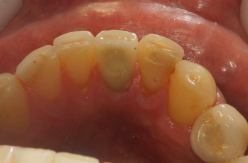

O paciente D.D.S., de 49 anos, me procurou no meu consultório indicado para a um tratamento de implante no elemento 41, devido a uma fratura ocorrida após o retratamento endodôntico (Figura 10).

Foi instalado um implante Due Cone de 3.5 x 13.0 mm, que foi estabilizado a 45 Ncm, e uma prótese provisória adesiva, instalada para permanecer durante as 12 semanas de espera para o segundo tempo cirúrgico (Figuras 11 e 12).